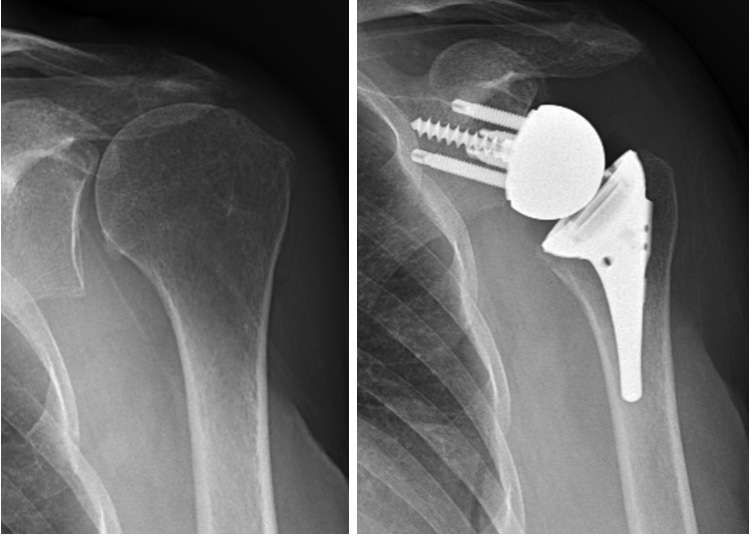

Rotator cuff tear arthropathy is a combination of massive unrepairable rotator cuff tear and glenohumeral arthritis. Many patients can be treated with activity modification, stretching exercises to restore and maintain shoulder motion, strengthening exercises, and oral anti-inflammatory medications. Cortisone injections can provide symptomatic relief.

When non-operative treatment fails to provide adequate pain relief and functional improvement shoulder replacement is an option. An anatomic humeral head replacement or humeral resurfacing can be performed in patients who are able actively (independently) raise their arm above their shoulder and have good strength. In most cases a reverse total shoulder replacement is performed to relieve pain and restore shoulder function.

Left shoulder with massive Left shoulder treated with reverse total shoulder rotator cuff tear and rotator cuff tear arthropathy

A reverse total shoulder replacement is specifically designed to be used in cases that do not have a functioning rotator cuff. The implants include a metal hemisphere that is attached to the glenoid/scapula and a metal humeral implant that has a plastic (polyethylene) socket.